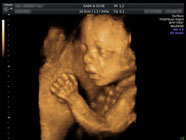

産科

当院では分娩は行っていませんが、里帰り出産の方や近隣施設で分娩をご希望の方に、妊娠後期まで妊婦健診を行っています。

どうぞお気軽にご相談ください。